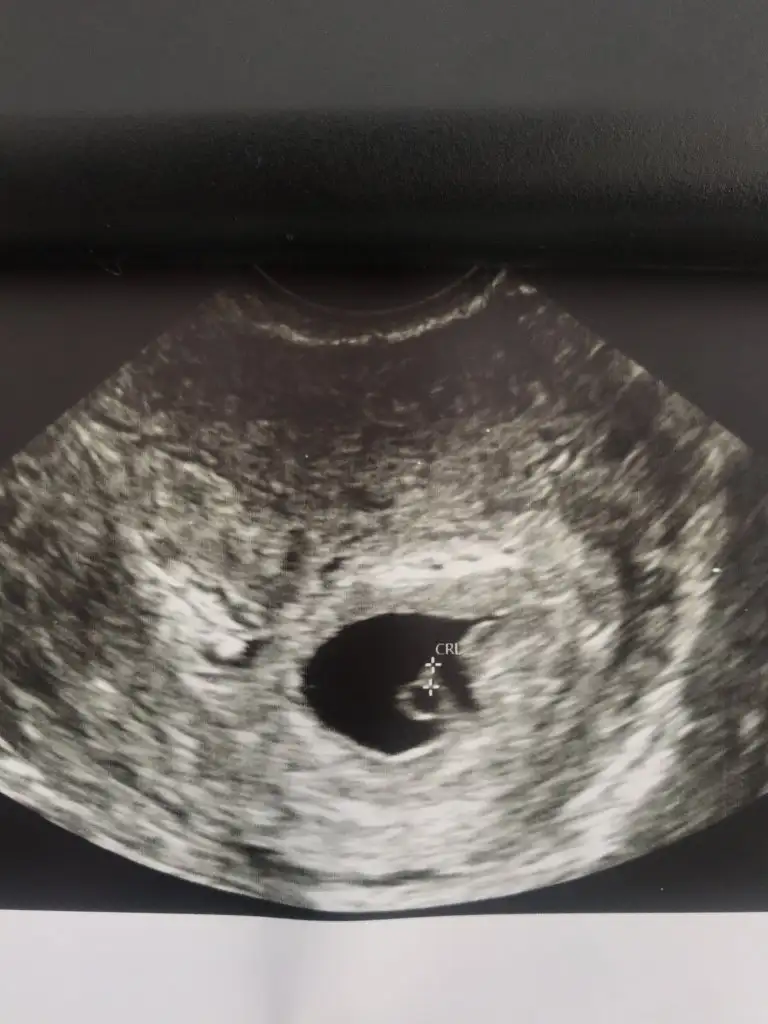

6+1 Gebelikte Yolk kesesi var bebek yok

40 yaşındayım. Sata göre 6+1 hamileyim.

Vajinal ultrasonda gebelik kesesi ve yolk sac var fakat bebek görünmedi. Dr'a göre haftaya da göremezsek sorun olma ihtimali yüksek.

Bu durumu yaşayan, bebeği daha geç gören var mı?